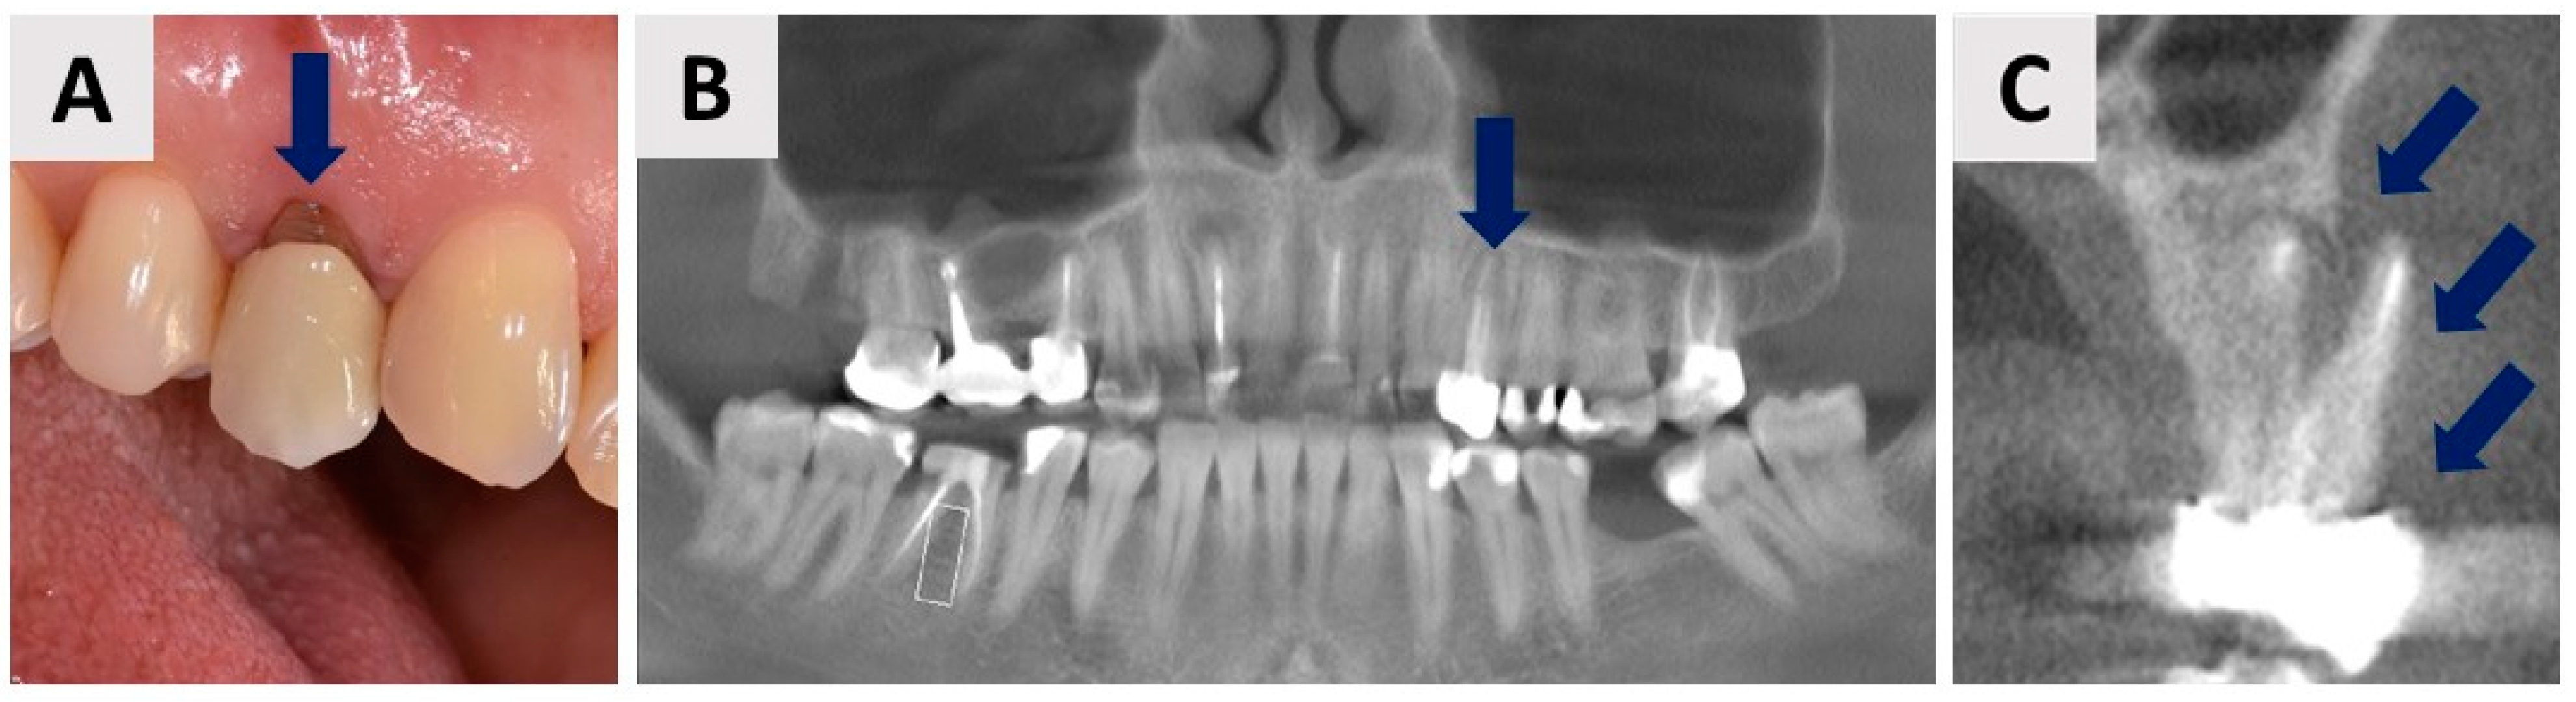

2.1. Patient Description, Case History, and Ethical Considerations

2.4. Healing Phase and Dental Implant Placement Planning